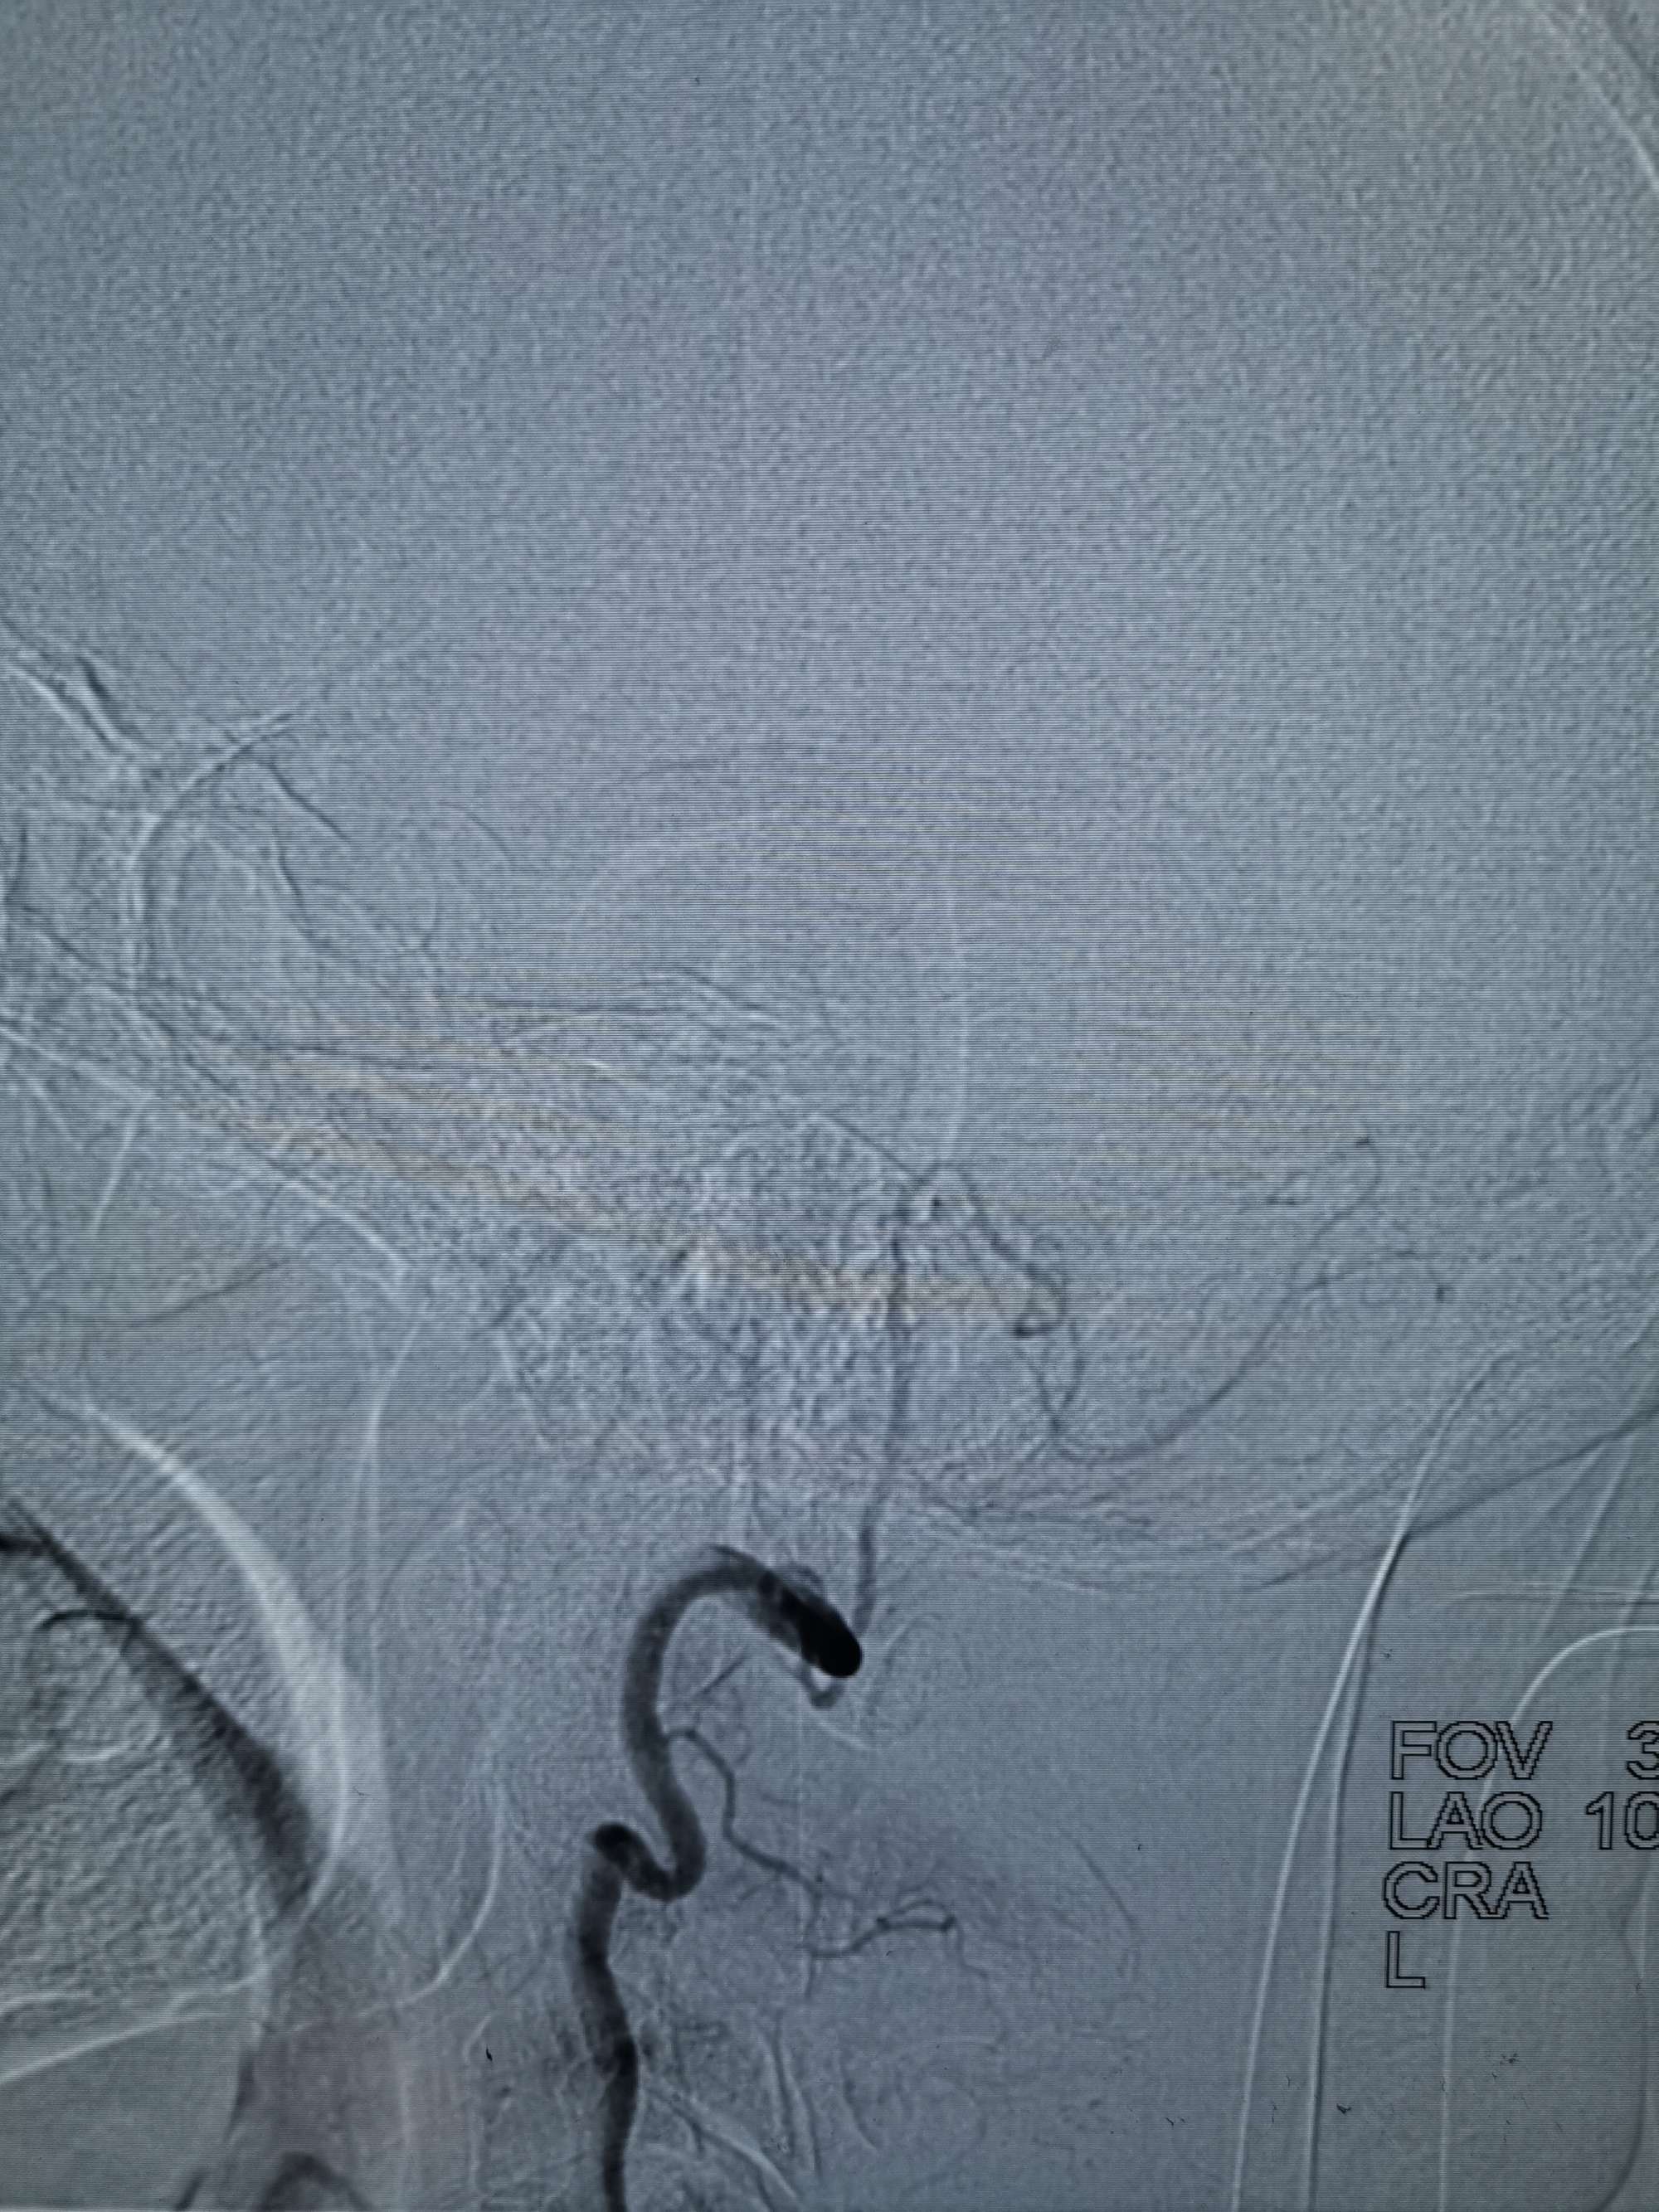

手术过程

在微导管支撑下先将微导丝和微导管穿过闭塞段,微导管超选造影证实位于基底动脉真腔后更换300cm外周交换导丝,撤出微导管后按从小到大,从远到近的原则行球囊扩张,本例手术选择了1.5✖️15、2.0✖️20、2.5✖️20球囊进行扩张,扩张满意后植入Enterprise支架,手术结束。